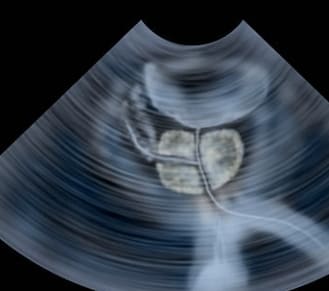

- 진단은 의사가 문진, 신체검사, 소변검사, 혈액검사, 초음파검사 등을 통해 진행합니다.

- 전립선 비대증은 나이가 들면서 전립선이 점차 커져서 요도를 압박하고 소변을 보기 어렵게 만드는 질환입니다.

- 전립선은 남성의 생식기관으로, 방광 바로 밑에 위치하며 소변과 정액의 배출을 돕습니다.